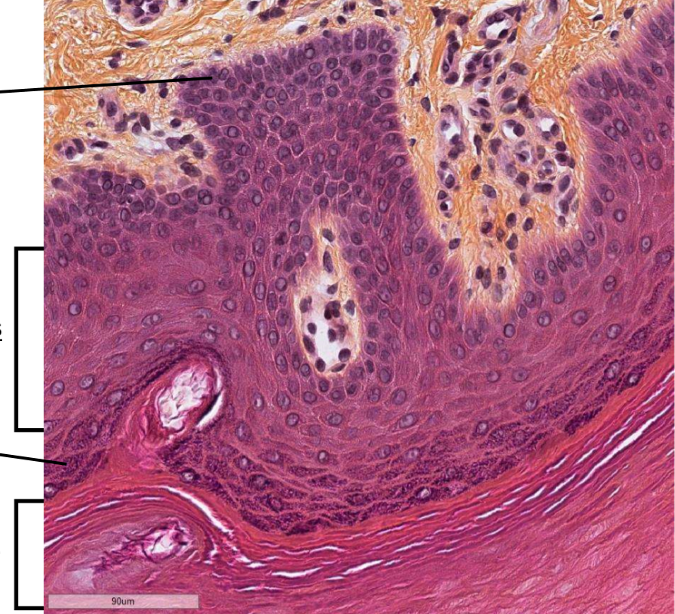

Lame, les keratinocytes migrent de ou vers ou, différencie les couches

lame de peau acral de l’orteil, on observe l’épiderme

migrent de facon ascendante (vers la surface de la peau)

couche basale: membrane basale avec des cellules souches qui font de la division mitotique, on y retrouve aussi les melanocytes

couche épineuse: desmosomes ++

couche granuleuse: granules de keratohyaline dans cytoplasme

couche cornée : squames de keratine aplatie, pas de noyau ni de cytoplasme